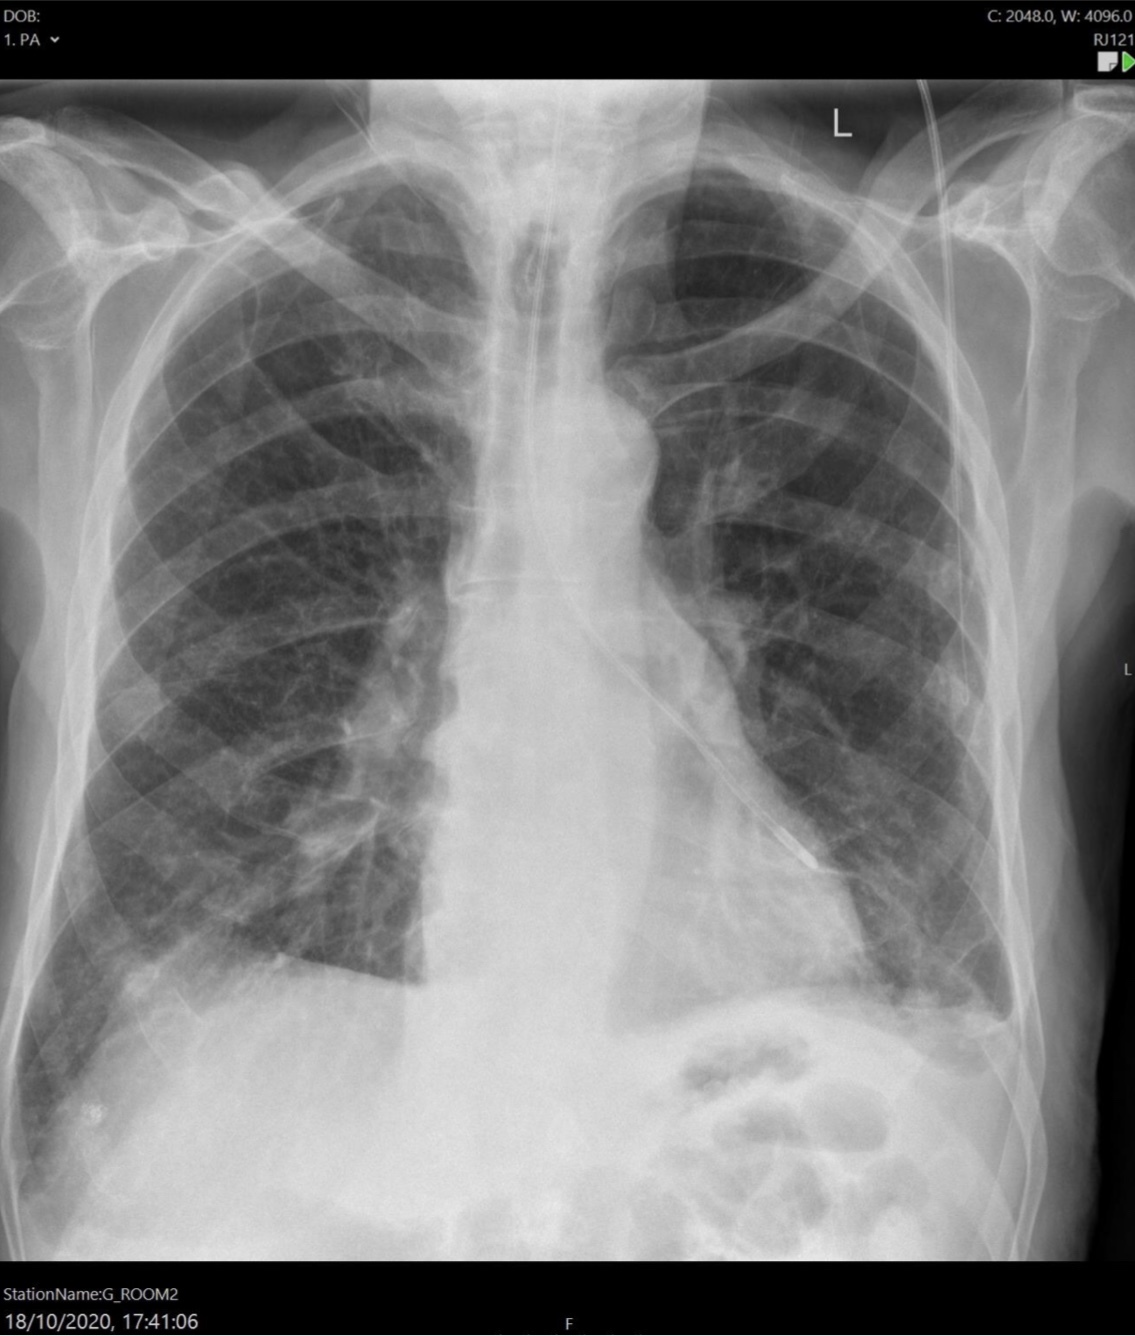

Cardiomegaly

Heart failure

Alveolar oedema

Dilated upper lobe vessels

Pleuarl effusion